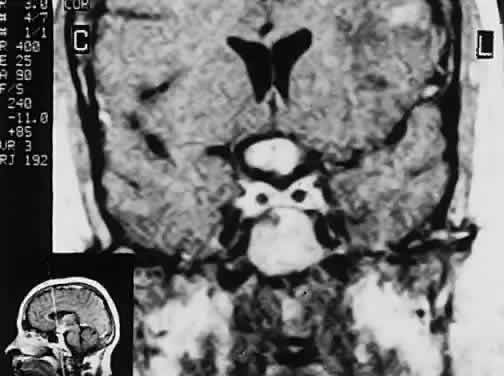

In previous decades, chiasmal interference with optic atrophy, but “normal” plain skull films, was referred to as “Cushing's syndrome of the chiasm,” caused by meningiomas, aneurysms, or other noncalcified suprasellar lesions. The modern neuroimaging techniques of enhanced CT, “bone-window” protocols, and gadolinium-contrasted MRI are now exceedingly sensitive in disclosing meningiomas or other parachiasmal masses (Fig. 4). At present, contrast-enhanced CT or MRI precisely demonstrate extra-axial tumor configuration; CT is superior in disclosing calcification or bone changes, but it is inferior for assessing suprasellar or intrasellar extension, postsurgical changes, and vascular displacement or encasement.76 Whether MRI or even MR angiography obviates standard selective arteriography, especially when surgical intervention is contemplated, is moot.

Fig. 4. Magnetic resonance imaging of a suprasellar meningioma (TR, 600 milliseconds; TE, 20 milliseconds). A. Coronal section of a large meningioma (large arrows), isodense to brain. B. Sagittal section. Note the normal sella and pituitary gland (p). Sagittal (C) and coronal (D) sections of a planum meningioma, extending into the sella. Note the upward deflection of the chiasm (arrow in C) and extension to the cavernous sinus (arrows in D).